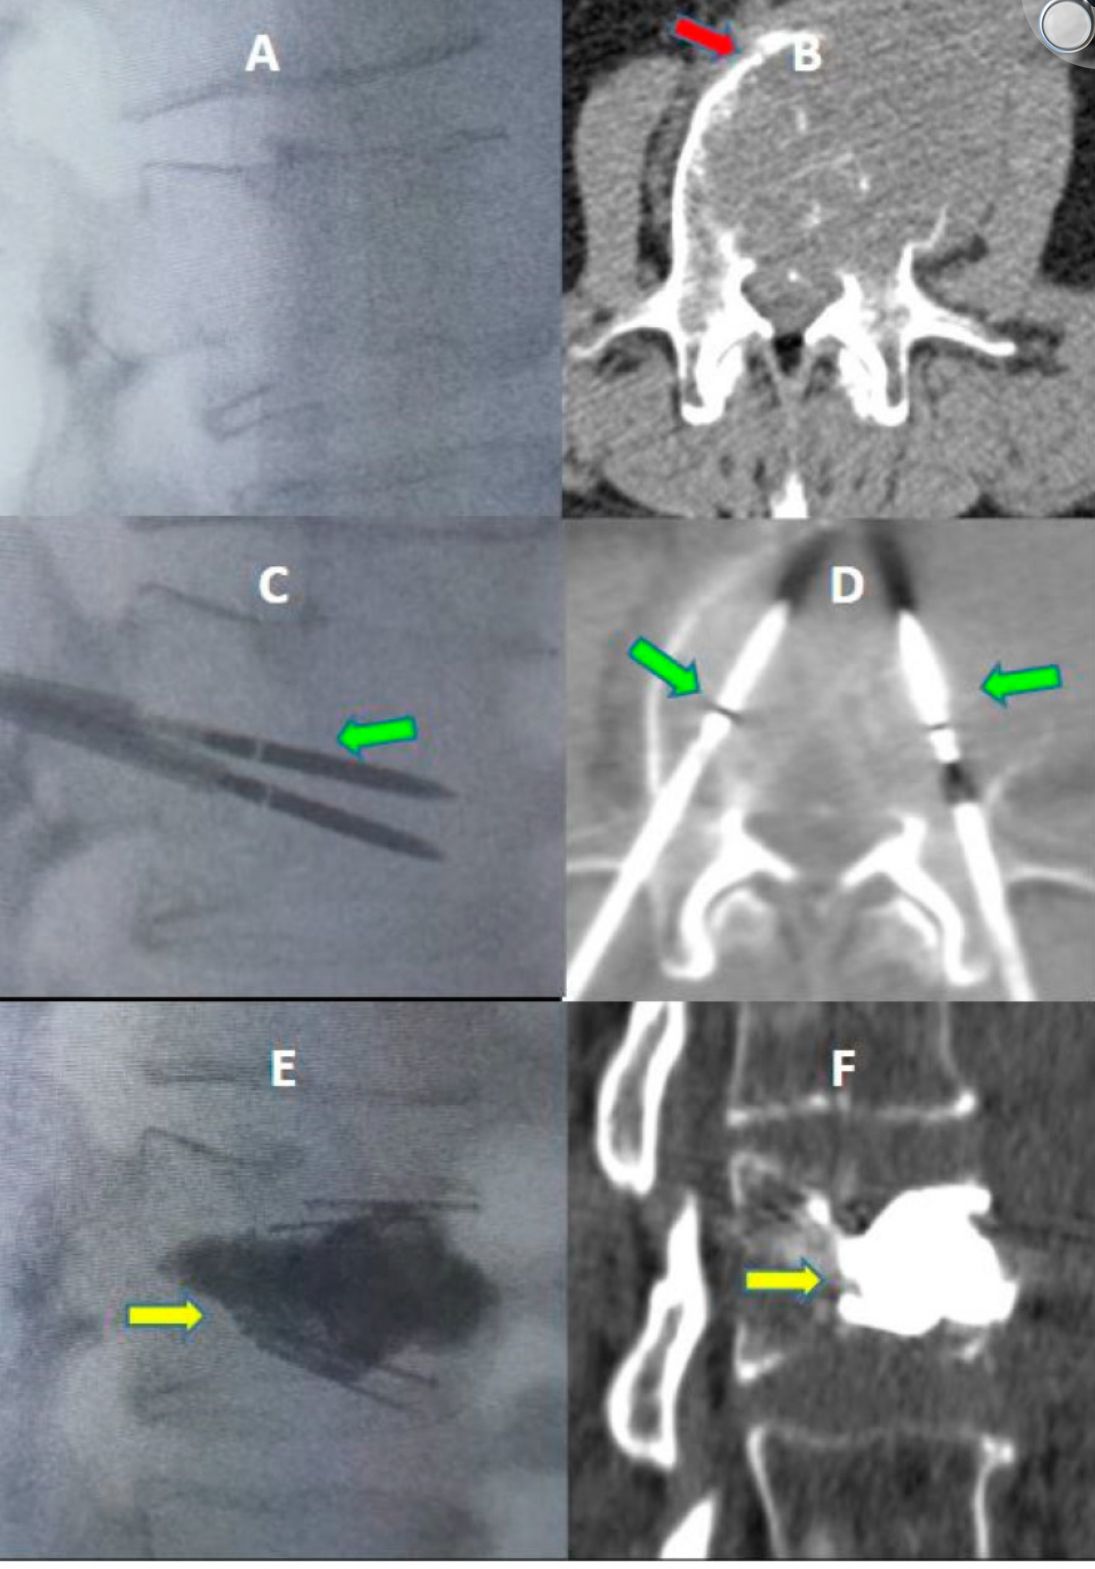

Dispongo de una especial dedicación al tratamiento de las lesiones vertebrales, tanto oncológicas como osteoporóticas, empleando técnicas avanzadas de vertebroplastia, cifoplastia y sistemas de expansión e implantes vertebrales (SpineJack®, tornillos percutáneos) que permiten restaurar la estabilidad de la columna y aliviar el dolor de forma inmediata.